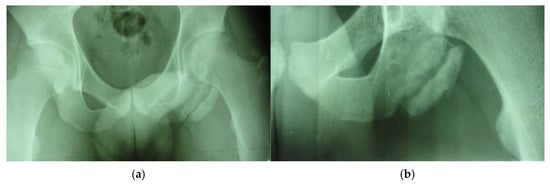

In the second case, the patient, a left back, experienced pain in the inguinal region and left thigh while running during a national team training session. This 23-year-old national team member has six years of experience as a first-league professional in Romania, standing 202 cm tall and weighing 105 kg. Pelvic radiography was incorrectly performed (incorrectly) and the patient was diagnosed with left thigh muscle damage. (Figure 4).

Figure 4.

Incorrect pelvic X-ray.

Three years post-trauma, the player develops symptoms of peripheral neuropathy with sensory and motor symptoms in the external popliteal sciatic nerve. Lumbar degenerative disc disorder or piriformis syndrome was suspected, and lumbar and pelvic MRI was performed.

The spinal MRI revealed no evidence of degenerative lumbar disc pathology or radiculopathy (Figure 5). Magnetic resonance imaging (MRI) and radiographic examination of the pelvis revealed an old avulsion injury with a detached bone fragment at the insertion site on the left ischial tuberosity, involving the semitendinosus, semimembranosus, and biceps femoris muscles (collectively referred to as the ischium-calf muscles). This condition has led to the development of pseudoarthrosis and bone edema at the level of the ischial tuberosity. The sciatic nerve is positioned tangentially to the inflammatory response. Despite the detachment, the bone fragment remains vascularized due to the maintained insertion of the ischial calf muscles, preventing it from becoming a bone splinter (Figure 6 and Figure 7).

Figure 7.

(a) Pelvic X-ray—ischial tuberosity, (b) ischial tuberosity X-ray—detail.

The pseudoarthritis secondary to the old ischial tuberosity avulsion can be visualized as follows:

- An old detached bone fragment with signal in the T1 and T2 ponderations, similar to the rest of the existing bone structures, but showing focal alterations of the PD fat sac and STIR hypersignal, indicating bone edema.

- Fluid accumulation in T2 hypersignal, T1 hyposignal, between the torn bone fragment and the remaining tuberosity

- The altered PD fat sac hypersignal in the sciatic nerve, adjacent to the inflammatory process, indicates changes suggestive of focal neuritis.